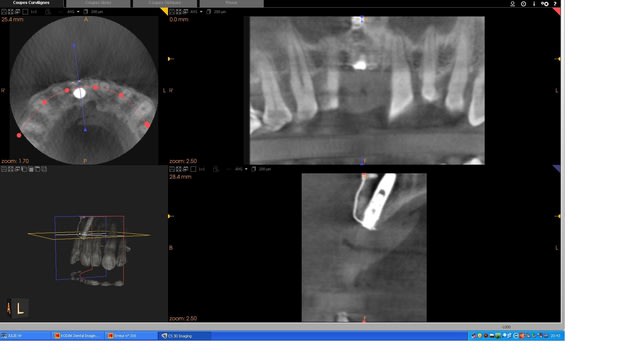

pour finir vous avez la 3D post op